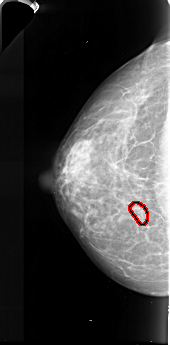

A_1022_1.LEFT_CC

LEFT_CC LINES 4831 PIXELS_PER_LINE 2371 BITS_PER_PIXEL 16 RESOLUTION 42 OVERLAY

FILE: A_1022_1.LEFT_MLO.OVERLAY

TOTAL_ABNORMALITIES 1

ABNORMALITY 1

LESION_TYPE CALCIFICATION TYPE PLEOMORPHIC DISTRIBUTION CLUSTERED

ASSESSMENT 4

SUBTLETY 3

PATHOLOGY MALIGNANT

TOTAL_OUTLINES 1

BOUNDARY

FILE: A_1022_1.LEFT_CC.OVERLAY